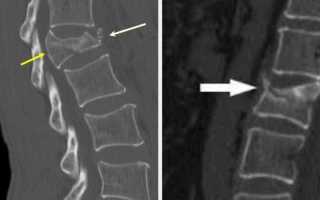

- Рентгенография в различных проекциях позволяет определить наличие смещения позвонков и повреждений костной структуры позвоночника.

- Магнитно-резонансная томография предоставляет наиболее полное представление о состоянии позвоночника. Этот метод помогает выявить повреждения спинного мозга, нервных корешков и сосудов, а также оценить состояние межпозвоночных дисков.

- Компьютерная томография позволяет детально изучить особенности перелома, а также повреждения мягких тканей и соседних органов.